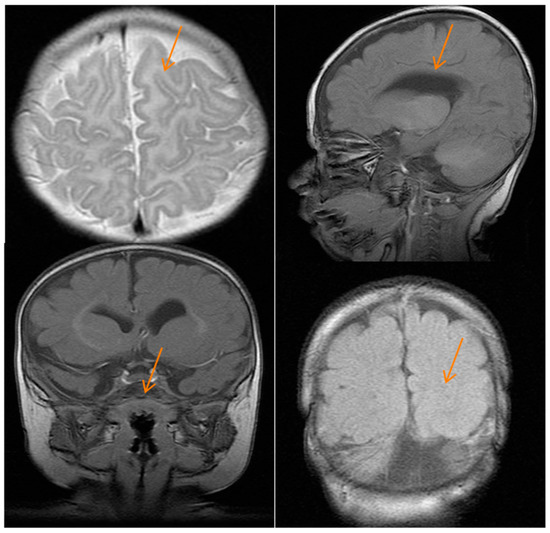

2.1. Case Report